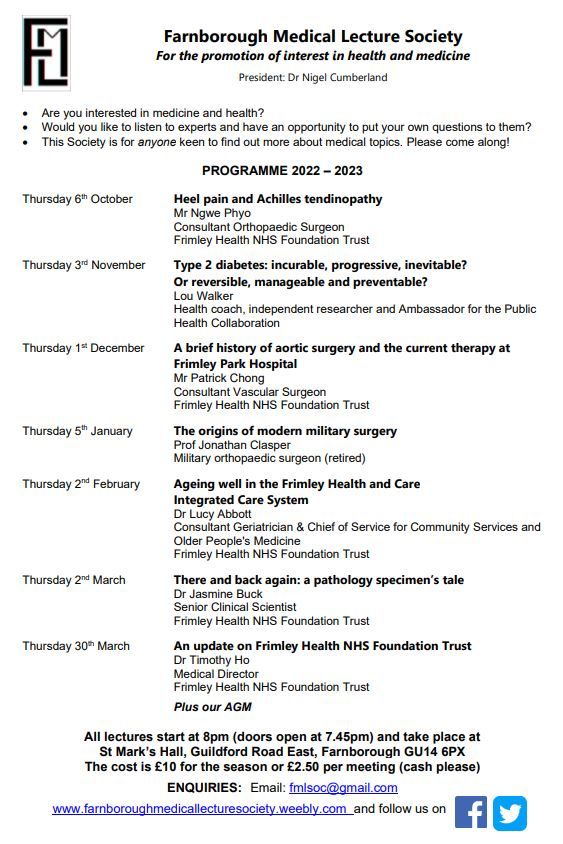

The AAA Screening West Surrey & North Hampshire celebrates 10 years of #AAA screening in West #Surrey and North #Hampshire. Join us as we celebrate the history & provision of aortic screening & surgery in our region on 1/12/22 at 8pm in #Farnborough. BBC Surrey @eagleradiouk247 Vascular Society FrimleyHealth&CareICS Frimley Health NHS Foundation Trust 💙